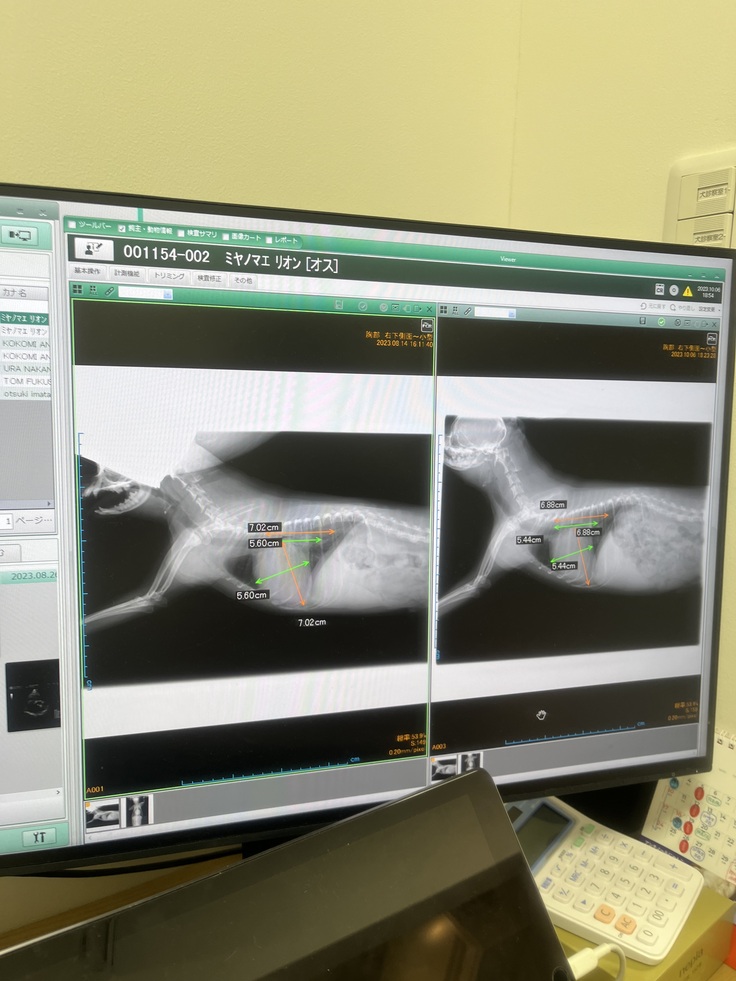

左が8/14 右が10/6

少し心臓が小さくなりました😌✨